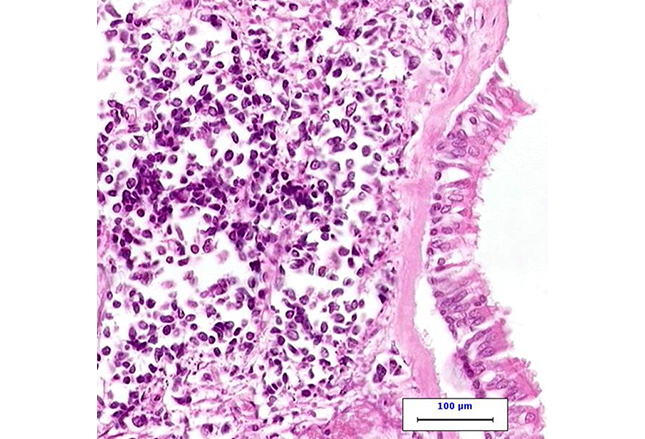

小细胞肺癌(SCLC)曾被认为是燕麦细胞癌。无论是临床学特征或是生物学特征上,SCLC与非小细胞肺癌(NSCLC)均有明显的不同。这张HE染色的高倍视野显微图片的左侧为SCLC,右侧为正常呼吸上皮细胞。

A、SCLC是一种恶性上皮肿瘤,由圆形、椭圆形或纺锤形并缺乏细胞质的小细胞组成。

B、组织学上来讲,SCLC分化程度较低,属于高等级神经内分泌癌。